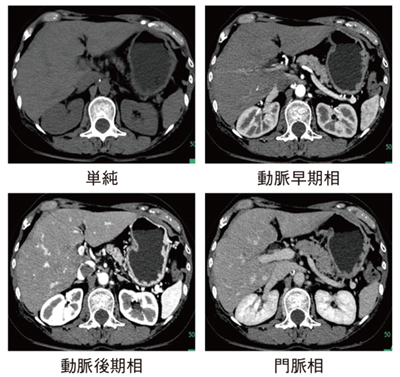

ヨード量を低減しつつ,注入量を維持して造影CT検査を施行した症例を提示する。161cm,55kgの男性で,eGFRは40mL/min/1.73m2であった。造影剤量を4割低減し,造影剤・生理食塩水同時注入法(190mgI/mL)にて3.5mL/s,97mL(28s)を注入,生理食塩水:3.5mL/s,20mLで後押しを行った。X線管電圧は80kVpとした。実際の画像を見ると,十分に読影可能な画質が得られている(図2)。

図2 造影剤を減量して造影CT検査を施行した症例